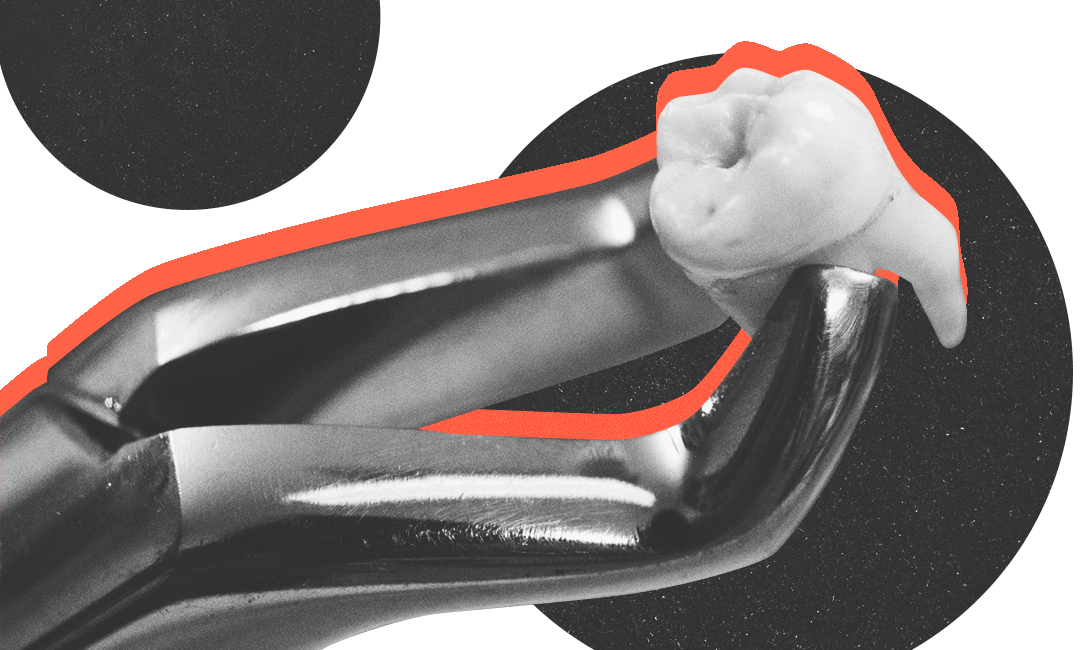

Современные технологии позволяют восстановить зубной ряд даже при полной потере зубов и атрофии костной ткани. Аутотрансплантация, или пересадка собственного зуба, – один из самых прогрессивных и безопасных методов восстановления. Донором в этом случае является здоровый зуб, который не несёт особой функциональной нагрузки, а именно зуб мудрости или сверхкомплектный зуб.

Аутотрансплантация проходит в три этапа: первый – удаление здорового зуба и сама трансплантация, второй – последующее лечение каналов – и третий – протезирование зуба коронкой или вкладкой. Чтобы приживление на новом месте прошло успешно, нужно аккуратно удалить зуб, сохранив периодонтальную связку, которой он крепится к костной ткани.

Не менее важно убедиться в том, что зуб-донор подходит по размеру к лунке зуба, который предстоит удалить. Для этого проводят предварительную примерку, распечатав трёхмерную модель зуба на 3D-принтере. Если форма и размер устраивают, можно начинать трансплантацию. Далее на рану накладываются швы, а пересаженный зуб осторожно фиксируется при помощи ортодонтической проволоки и резиновой тяги.